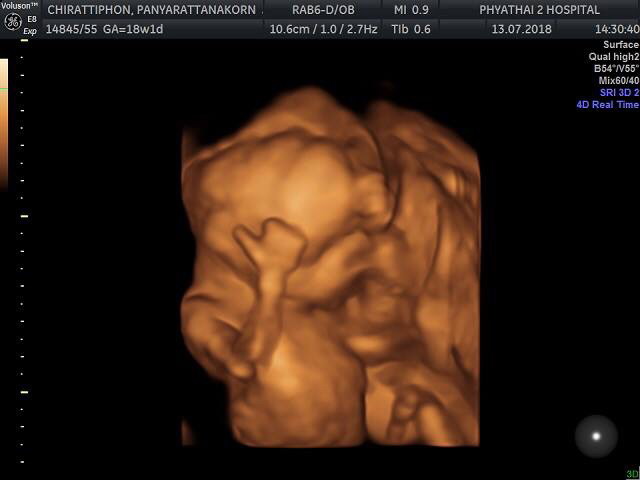

18+5week คลอด10มกรา ผู้ชายคับ♂️